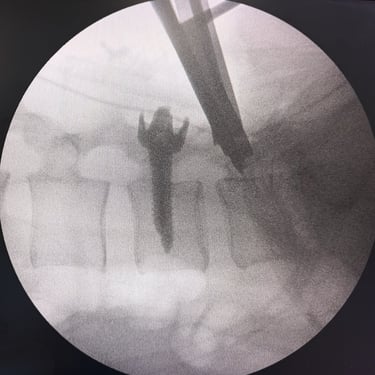

Manejo quirúrgico de la hernia lumbar con inestabilidad: enfoque moderno con FTP y TLIF

La hernia lumbar con inestabilidad vertebral es una patología frecuente que causa dolor lumbar persistente, ciática y limitación funcional, afectando la calidad de vida del paciente. Cuando el tratamiento conservador no logra resultados adecuados, la cirugía se convierte en la mejor opción terapéutica. La fijación transpedicular con tornillos (FTP) junto con la técnica TLIF (Transforaminal Lumbar Interbody Fusion) permite estabilizar la columna, descomprimir las estructuras nerviosas y lograr una adecuada fusión ósea. Este abordaje, especialmente mediante técnicas mínimamente invasivas (MISS), ofrece múltiples beneficios, como menor daño muscular, menor dolor postoperatorio y recuperación más rápida, facilitando el retorno temprano a las actividades cotidianas con mejores resultados clínicos.